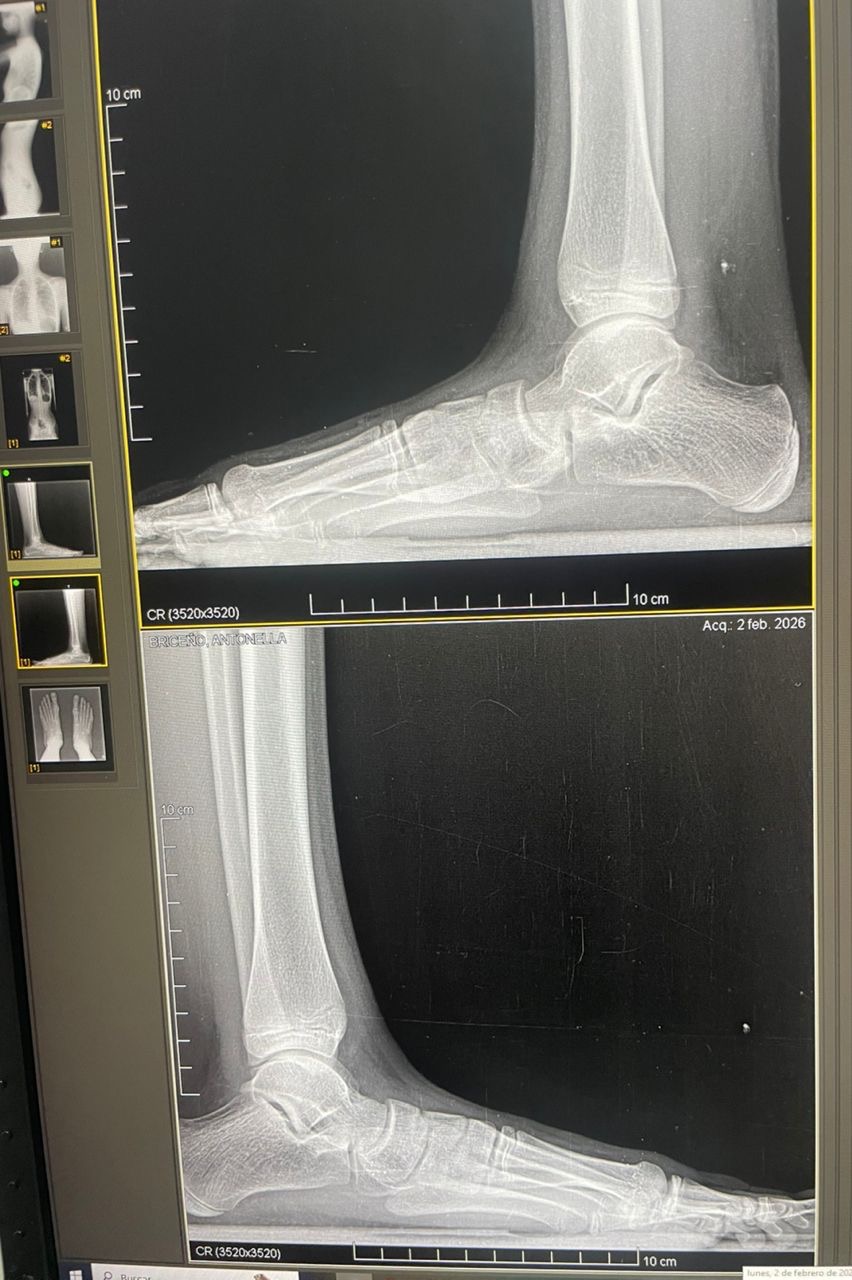

Estoy sufriendo una deformidad en los pies acompañada de pérdida del arco plantar, lo que le provoca dolor constante, dificultad para caminar y cansancio que me afectan en mi día a día mi crecimiento y desarrollo.

Los médicos han confirmado que necesito una cirugía correctiva especializada, la cual es fundamental para evitar que la condición empeore y así tener la oportunidad de disfrutar de una vida plena, saludable y sin dolor.